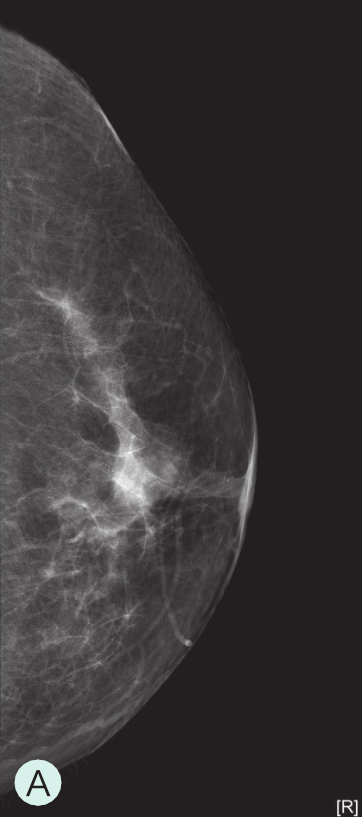

A级:几乎完全为脂肪型(图1-3-1A、图1-3-2A、图1-3-3A)。

图1-3-1 乳腺X线不同乳腺密度

A.脂肪型;B.散在致密型;C.不均匀致密型;D.极度致密型

B级:散在纤维腺体致密型(图1-3-1B、图1-3-2B、图1-3-3B)。

C级:不均匀致密型(可能掩盖小肿块)(图1-3-1C、图1-3-2C、图1-3-3C)。

D级:极度致密型(降低乳腺钼靶摄影的敏感性)(图1-3-1D、图1-3-2D、图1-3-3D)。

图1-3-2 乳腺超声不同乳腺密度